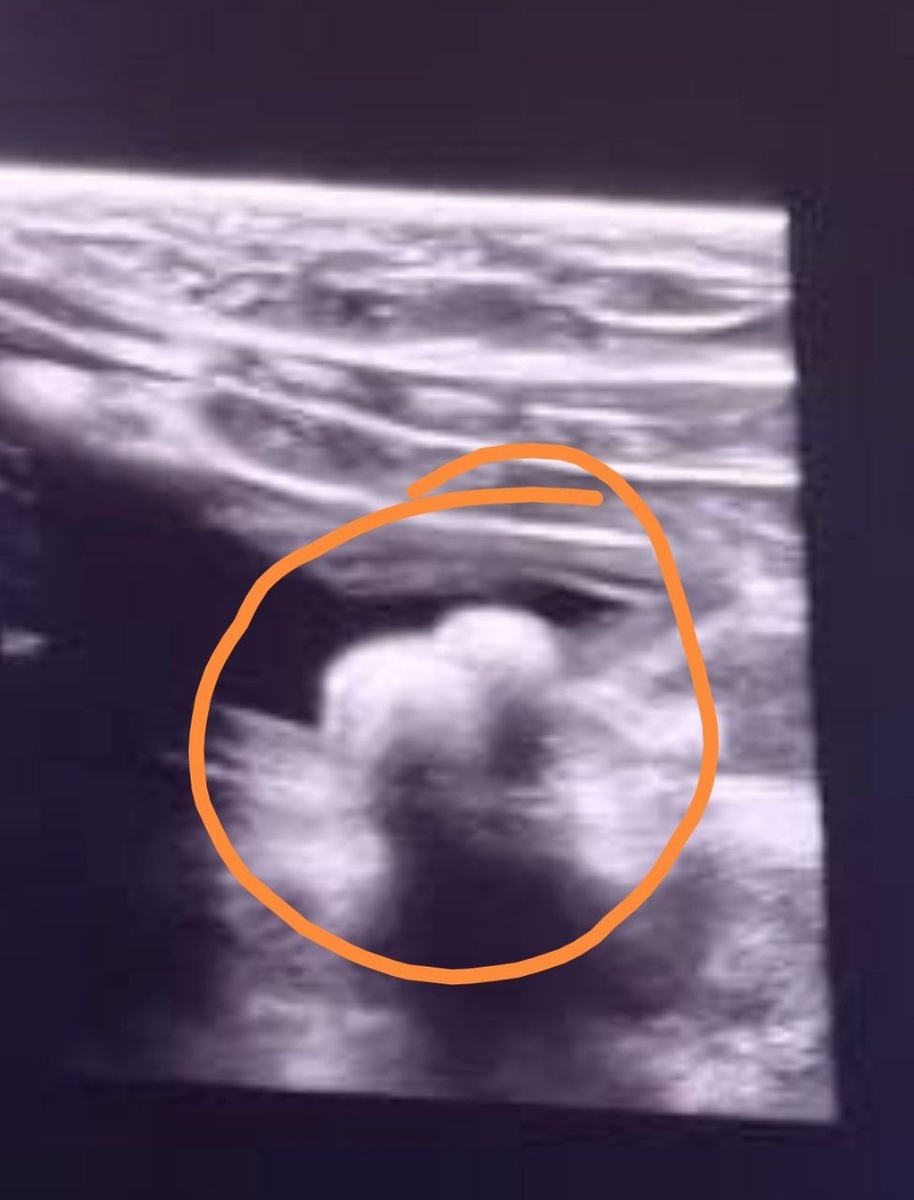

Наша Софочка снова очень нуждается в помощи🙏. У кошечки ухудшилось состояние, стала опять часто ходить в лоточек. Зная её многолетние проблемы с этим делом, обратились к врачу и на УЗИ обнаружили два камня в мочевом😔😔.

Также у Софочки опять взяли мочу на анализ, чтобы определить структуру камней для точно подобранного лечения и корма. Возможно даже потребуется оперативное вмешательство, так как камни внушительных размеров.